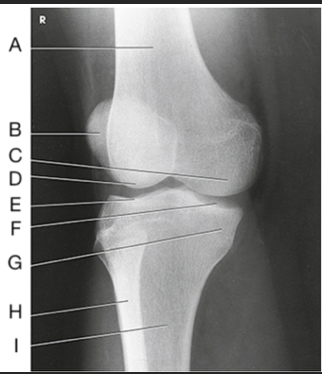

Name this projection

AP oblique medial rotation

What is demonstrated?

Lateral aspect (distal femur, patella, lateral tibial condyle, fibular head, and proximal tibiofibular joint)

What joint is demonstrated?

Proximal tibiofibular joint

Label the image: A

patella

Label the image: B

medial femoral condyle

Label the image: C

lateral femoral condyle

Label the image: D

medial tibial plateau

Label the image: E

Lateral tibial plateau

Label the image: F

medial tibial condyle

Label the image: G

lateral tibial condyle

Label the image: H

tibiofibular articulation

Label the image: I

fibula

Label the image: J

tibia